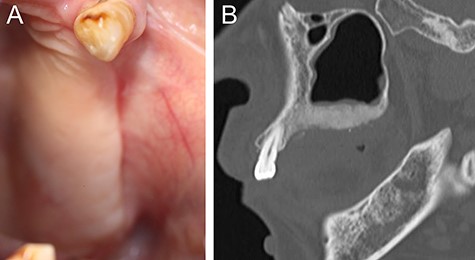

(A) Intraoral photograph showing gingival fistulas in #25 and #26 extraction sites (arrows). (B) Sagittal section of CT image showing separated sequestrums in the left maxilla (arrow) and bone resorption in the periapical area of #24 (arrowhead).

At 1 year after the extractions, a purulent discharge and exposed bone with gingival fistulas were observed in the extraction sites (Fig. 2A). CT images revealed separated sequestrums in the left maxilla and bone resorption in the periapical area of the left maxillary first premolar (FDI #24) (Fig. 2B). With the permission of the patient’s attending physicians, the alendronate was withdrawn. After exposed bone had been observed for 8 weeks, the patient was clinically diagnosed with Stage 2 BRONJ accompanying FD of the left maxillary bone. Under general anesthesia, we first performed extraction of #24 and sequestrectomy. We then performed a partial resection of the FD because necrotic-like bone fragments were collected by curettage of the marginal bone (Fig. 3). Finally, the surgical wound was completely closed by sutures. The histopathological diagnosis was chronic osteomyelitis with FD (Fig. 4). At 2.5 years after the operation, the healing is uneventful although residual FD bone exists (Fig. 5). Although local conditions permit the resumption of alendronate, it remains discontinued at the attending physicians’ discretion.